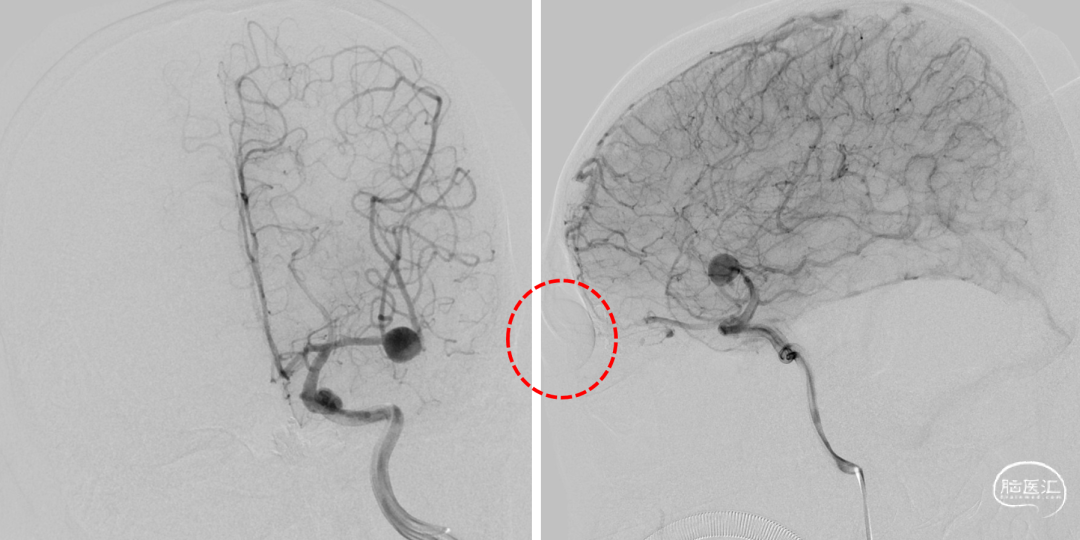

一期治疗

治疗经过

二期治疗